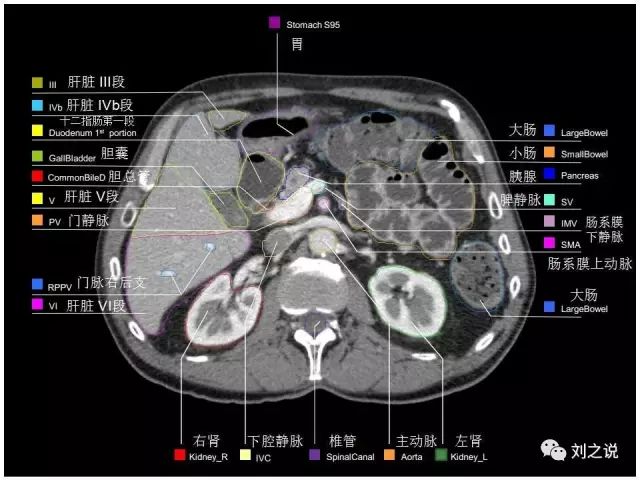

【解剖】高清实用 腹部CT断层

参考RTOG共识和3D-body解剖。

来源:刘之说